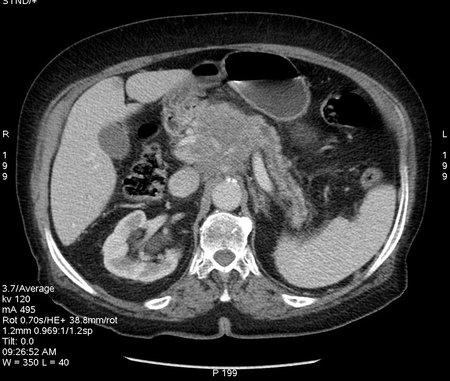

Пожилая женщина с болями в эпигастральной области.

Тумор тела с прорастанием в чревный ствол и верхние мезентериальные сосуды.

Продольное сканирование панкреас

Поперечное сканирование панкреас на уровне ее тела